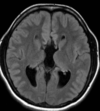

63 anos, Mulher, Hiponatremia corrigida, Hipotireoidismo.

Sindrome de desmielinização osmótica Mielinolise extrapontina (20% dos casos)

Qual o padrão da Mielinolise pontina e extrapontina?

Local: Ponte isolada (50%); Ponte + extraponte (30%) e extrapontina isolada (20%); Achado: Hiperintensidade central T2 na ponte, poupando os tratos corticoespinais dando aspecto de sinal do tridente; restrição a difusão é o mais precoce achado; Localizações extrapontinas: núcleos da base; mesencéfalo e substância branca;